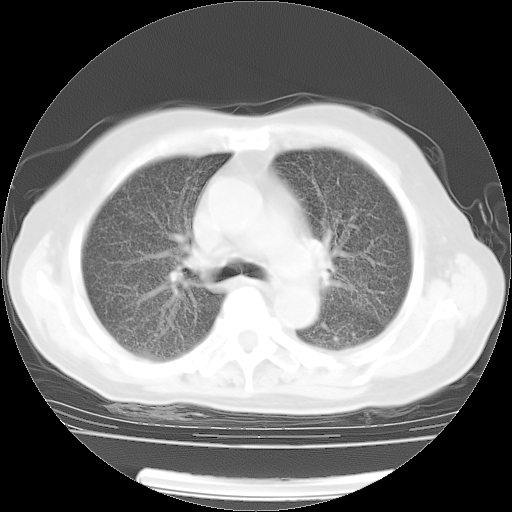

4月14日肺部CT